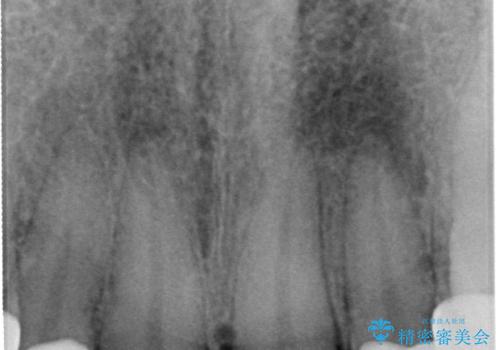

- 転んで欠けてしまった前歯を治したいと来院された患者様です。

この機会に、白くきれいにしたいとの事でした。

まず仮歯に置き換え、最終的な被せものの前に仮歯で形などを調整します。

その後精度の高いシリコーンによる型どりを行います。

歯の神経は生きていますが、精度の高い被せもののため冷たいものがしみるなどの症状もなく、きれいになったと満足していました。